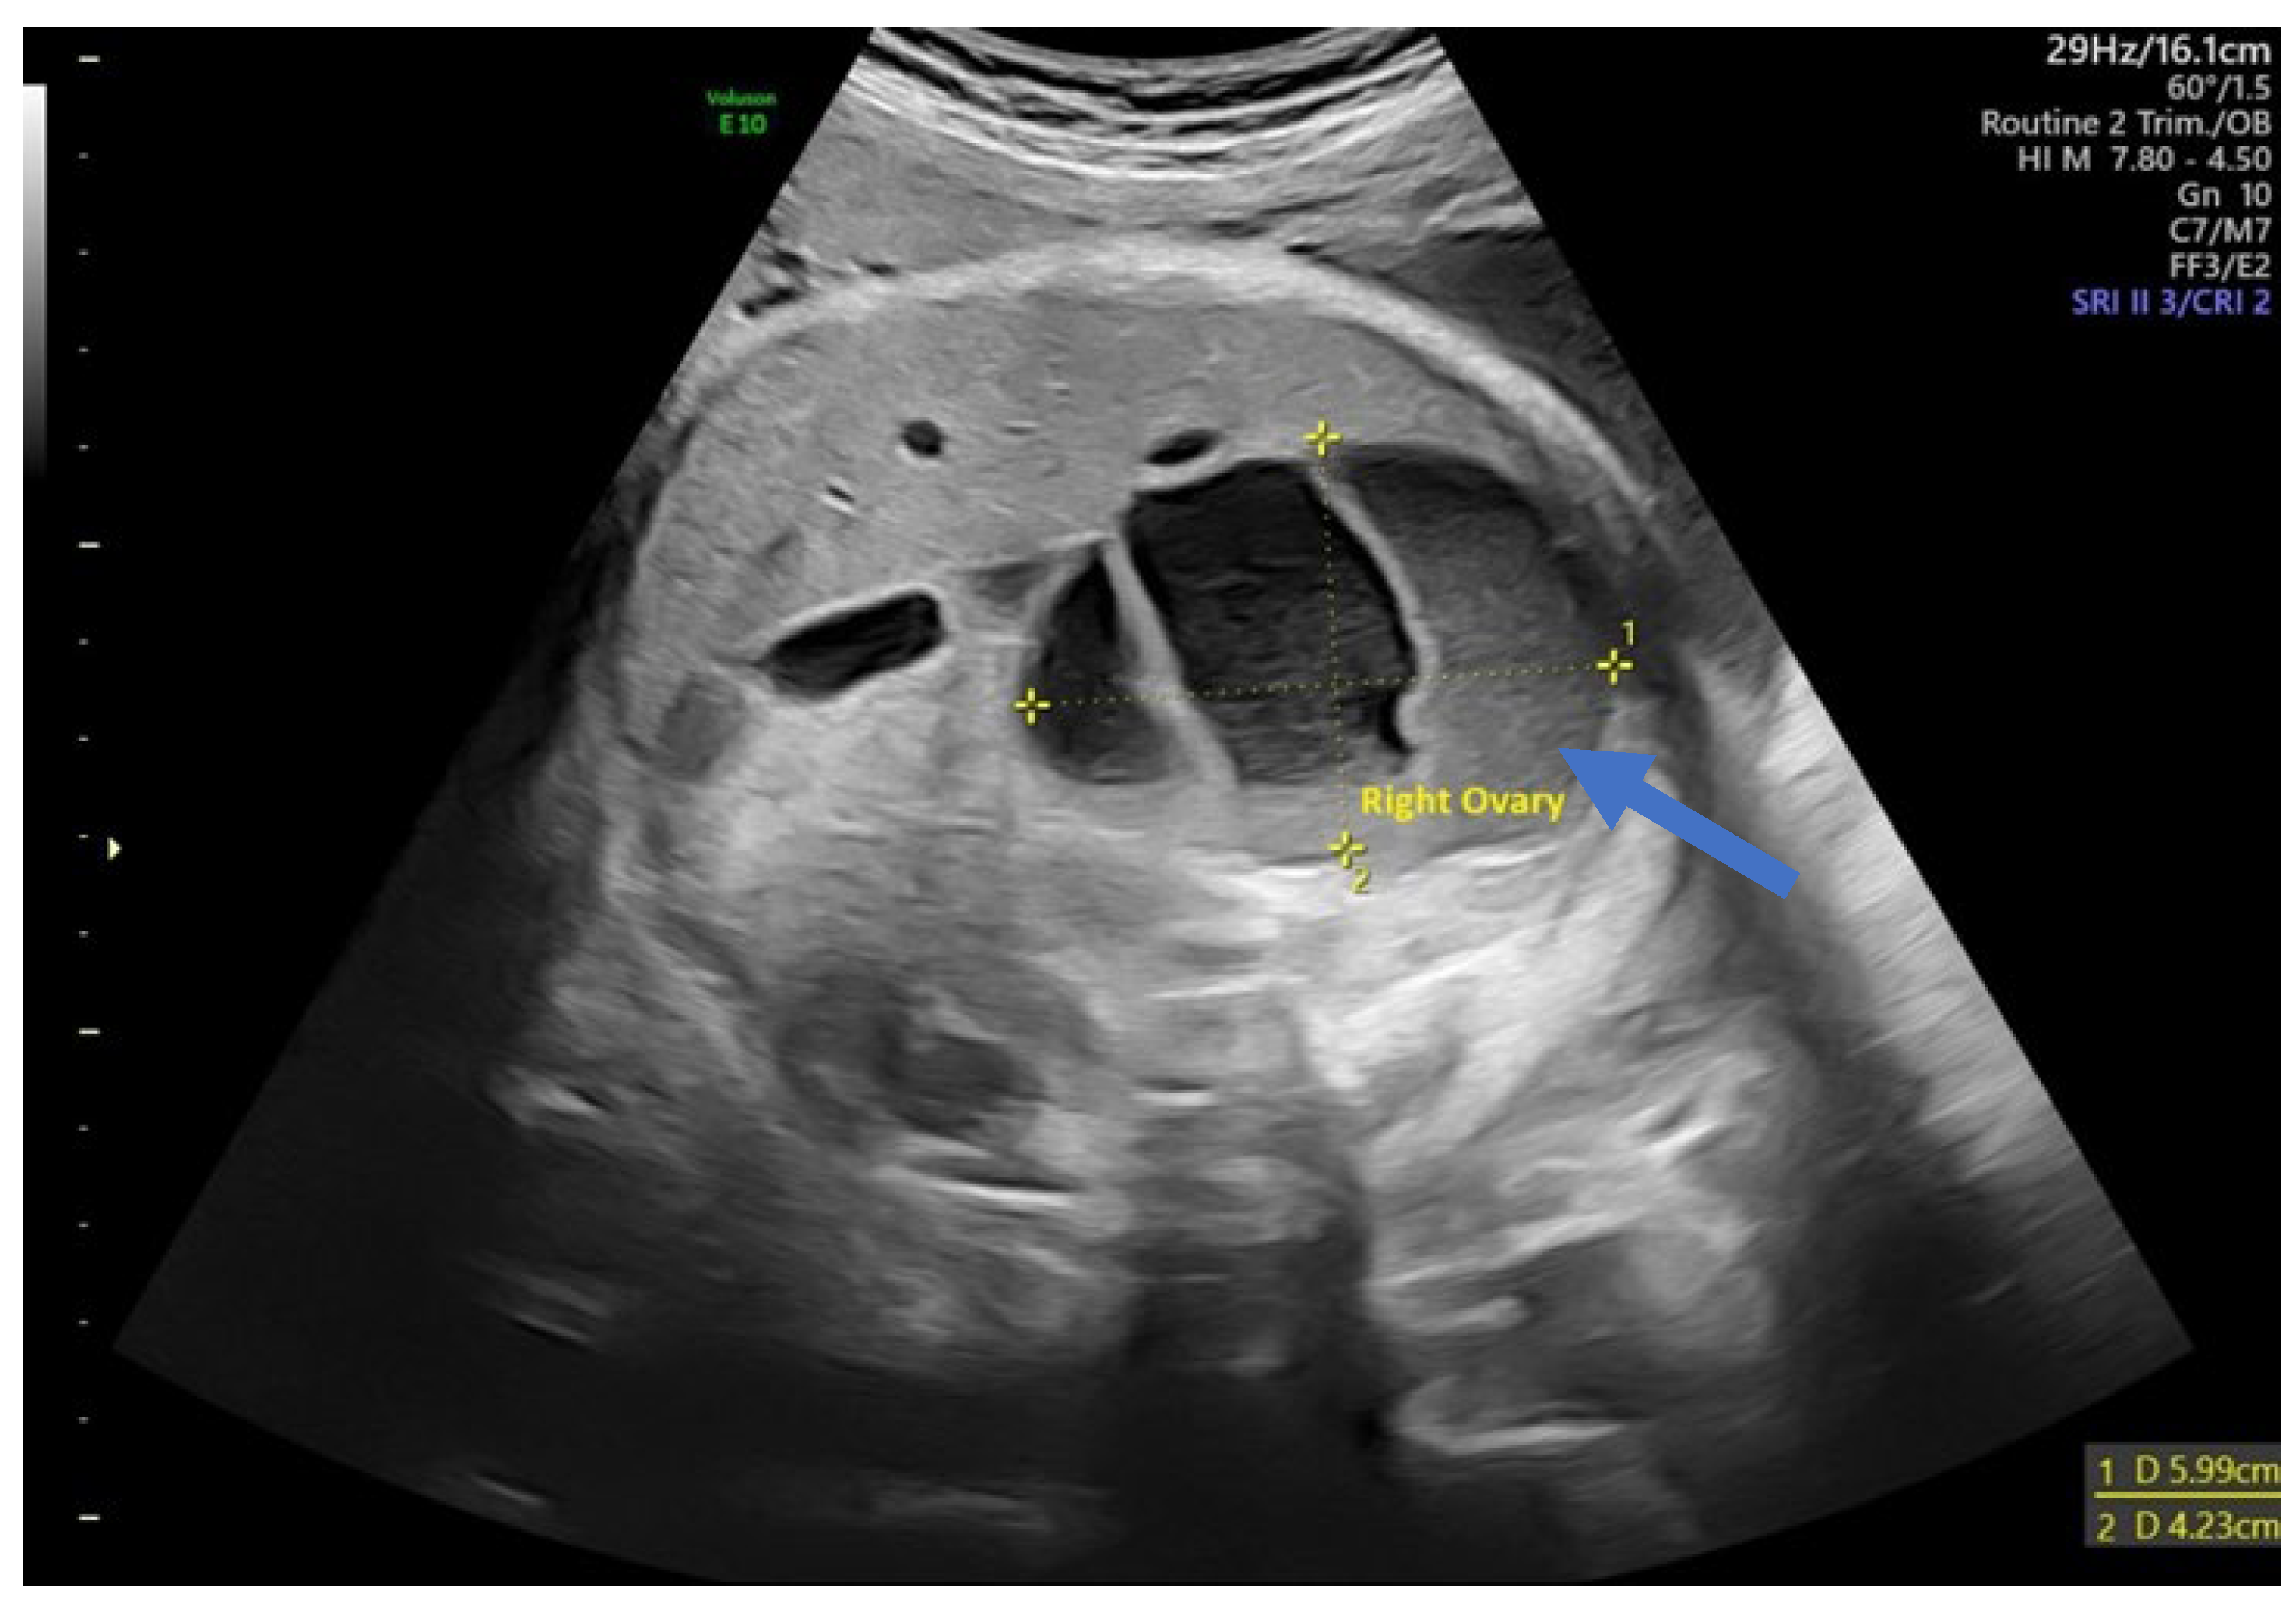

In 25% of cases, the cyst had the appearance of a complex cyst. On ultrasound, we observed the presence of internal echoes, indicating the presence of intracystic hemorrhage with round or crescent-shaped echogenic areas due to retraction of intracystic clots. We also noted fluid levels (liquid level) and sometimes the presence of microcalcifications at the level of the cyst walls (Figure 4).

Figure 4.

Ultrasound axial view. Right ovarian complex cyst in the 32nd week of pregnancy with a size of 6/4 cm and an echolucent stratification (arrow) corresponding to a hemorrhagic ovarian cyst.